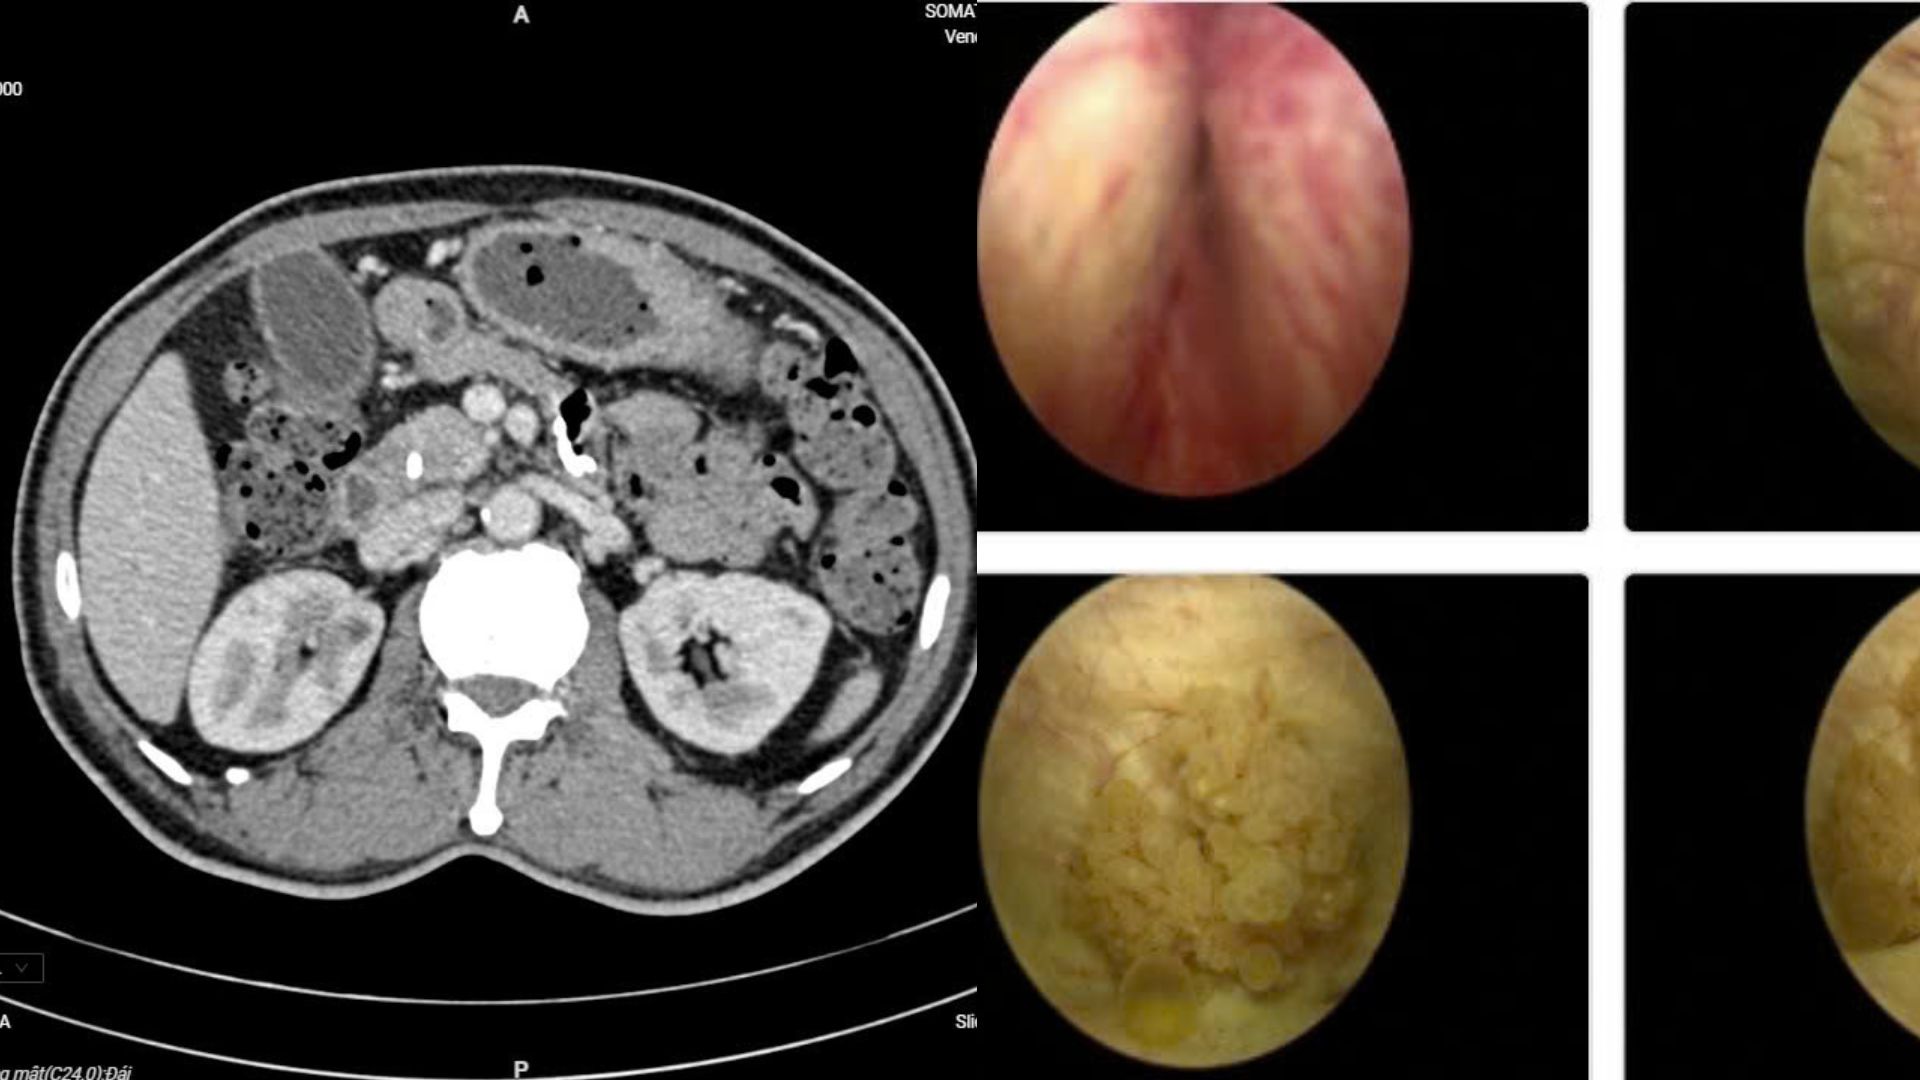

Người bệnh Đ.V.L nhập viện với biểu hiện đau bụng lâm râm kéo dài kèm vàng da nhẹ. Các xét nghiệm chuyên sâu và chẩn đoán hình ảnh cho thấy ông mắc đồng thời ung thư bàng quang và ung thư ống mật chủ – hai bệnh lý ác tính hoàn toàn khác biệt. Điều đáng nói là trước đó, người bệnh gần như không có dấu hiệu đặc trưng nào.

Các chuyên gia đã tổ chức hội chẩn liên chuyên khoa, thống nhất phương án phẫu thuật nội soi đồng thời cả hai bệnh ung thư. Đây là ca bệnh hiếm gặp, bởi việc can thiệp cùng lúc hai cơ quan khác nhau đòi hỏi trình độ chuyên môn cao và sự phối hợp chặt chẽ giữa nhiều chuyên ngành.

Ê-kíp gồm các chuyên khoa Tiết niệu, Gan mật tụy, Chẩn đoán hình ảnh và Giải phẫu bệnh đã phối hợp theo mô hình “teamwork”. Người bệnh được chỉ định cắt u bàng quang qua nội soi ngược dòng và phẫu thuật cắt khối tá tụy bằng nội soi ổ bụng.

Kết quả bệnh nhân cùng lúc mắc hai căn bệnh ung thư.